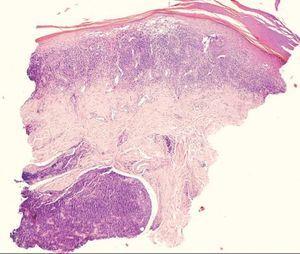

La biopsia mostraba una epidermis con características similares al liquen plano: desaparición de la capa basal, hipergranulosis en forma de «V», elongación de las crestas interpapilares en forma de dientes de sierra y presencia de cuerpos coloides en la interfase dermoepidérmica (fig. 2). Lo más llamativo desde el punto de vista histológico era la intensidad del infiltrado linfoide, que ocupaba toda la dermis papilar y se extendía hasta la dermis reticular alta, borrando la interfase dermoepidérmica y afectando además la dermis perianexial, formando un denso cúmulo linfoide alrededor de las glándulas sudoríparas (fig. 3). Estos linfocitos no presentaban atipia nuclear ni tendencia al epidermotropismo (fig. 4).

Figura 3.